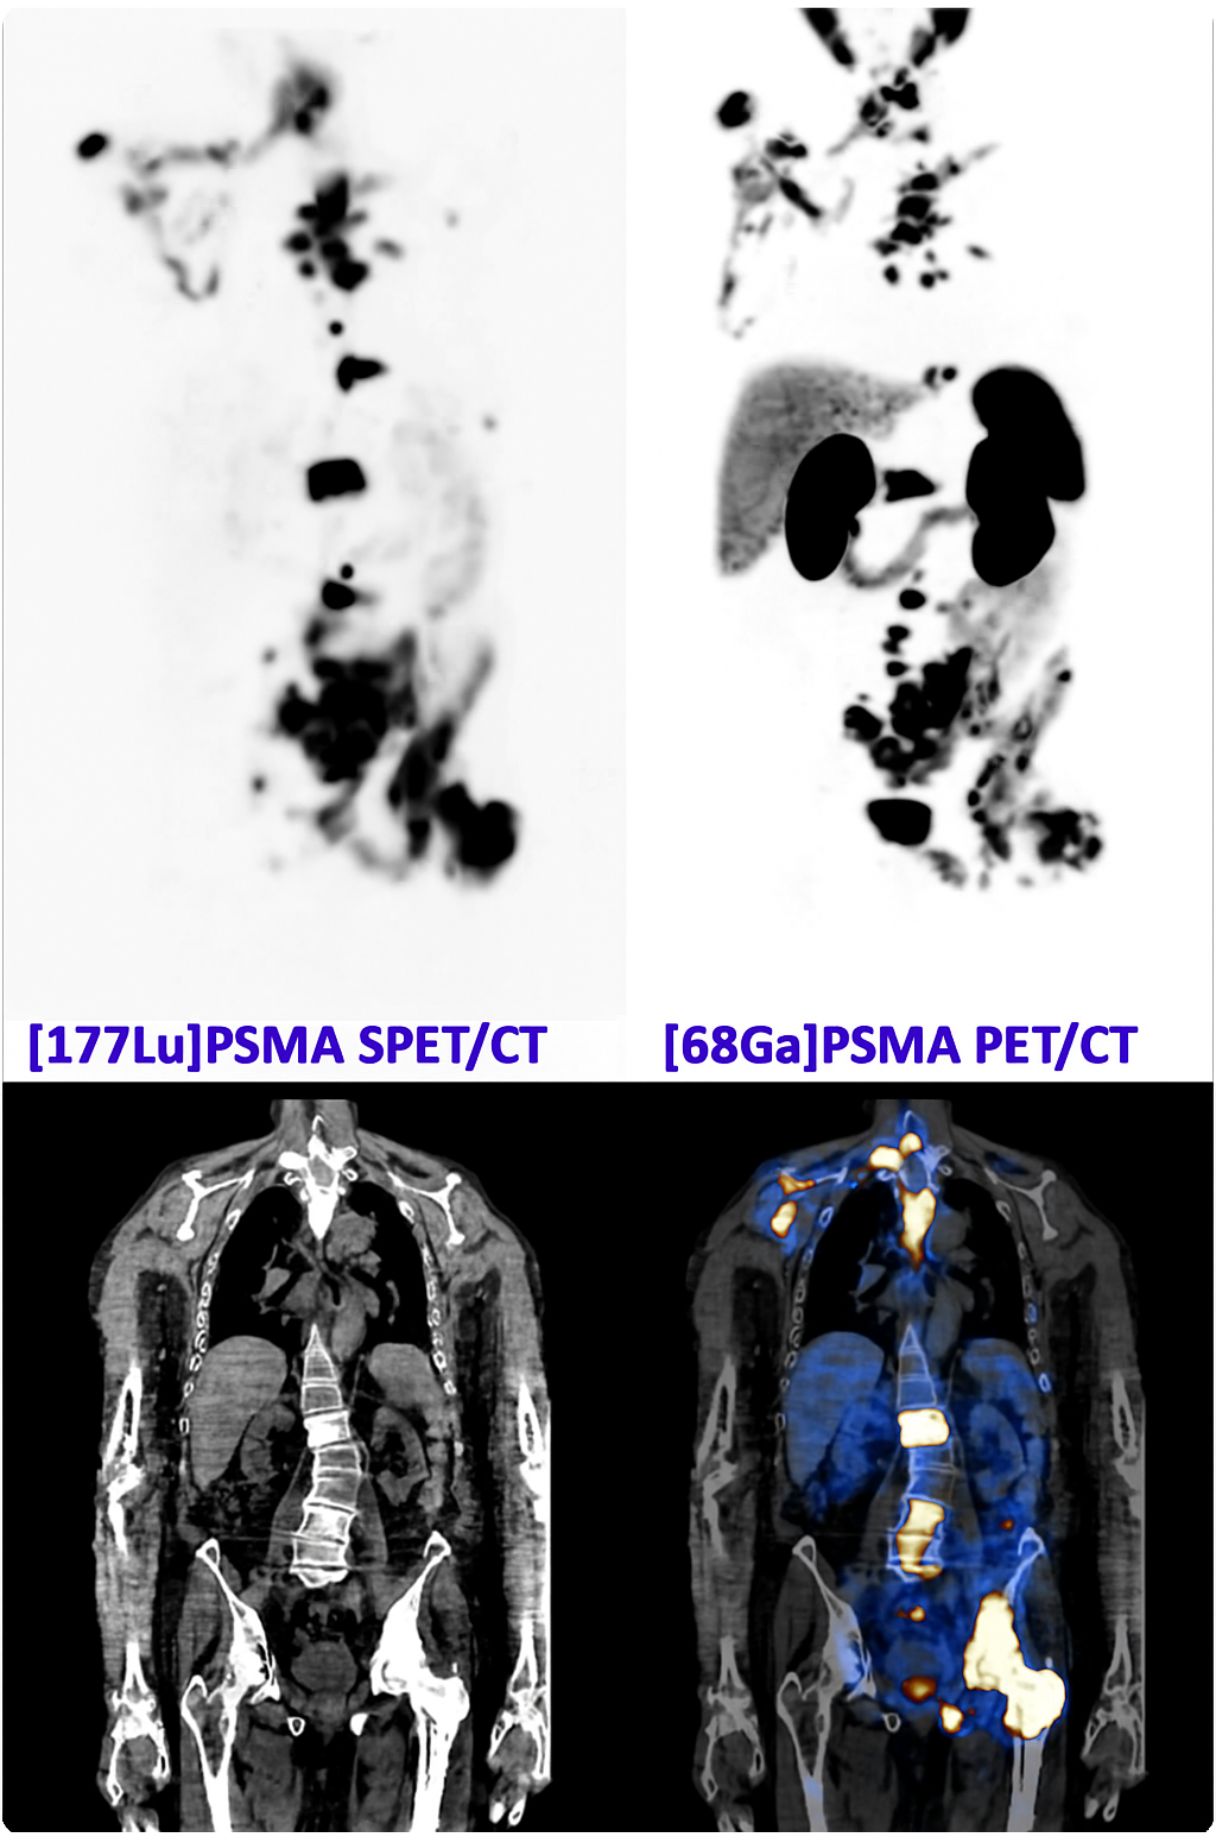

Caso condiviso da Saima Mushtaq

Paziente con anamnesi di malattia coronarica e pregresso impianto di stent sulla discendente anteriore sinistra.